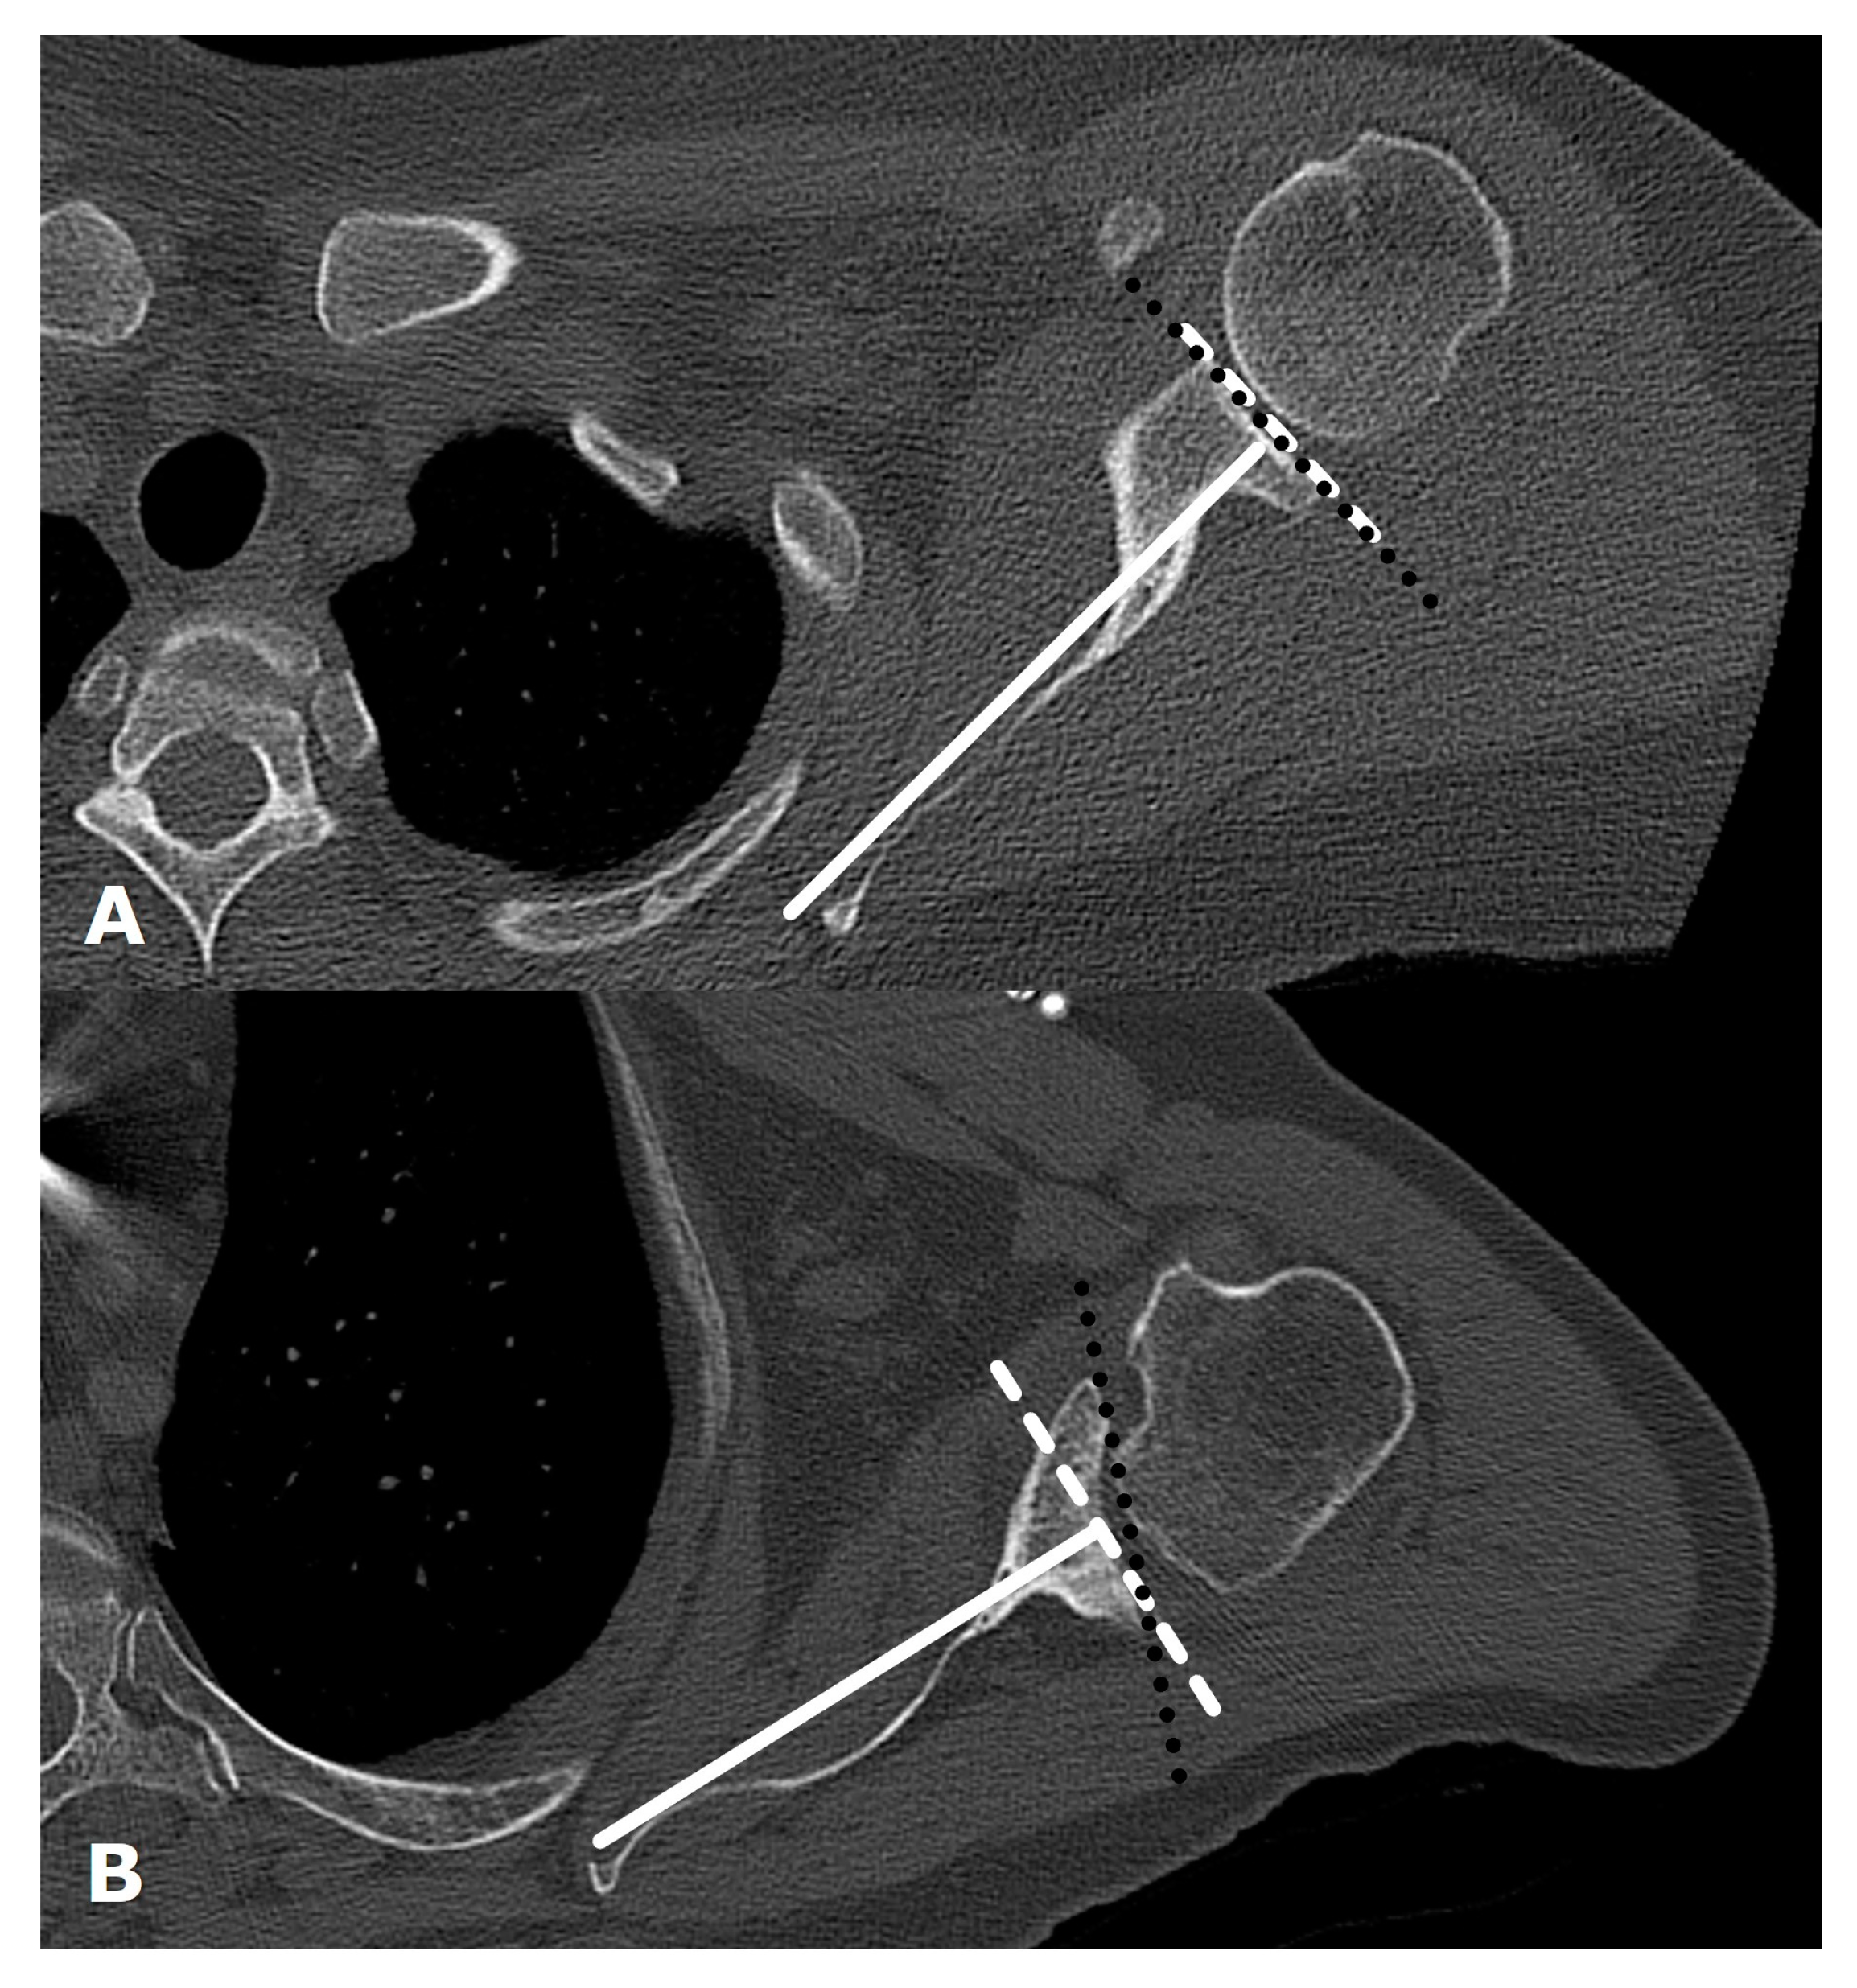

3. Preoperative Imaging

| Type | Description |

| B1 | No glenoid erosion; posteriorly subluxed humeral head with posterior joint space narrowing and osteophytes. |

| B2 | Biconcave glenoid due to posterior erosion and retroversion, with posteriorly subluxed humeral head. |

| B3 | Monoconcave glenoid with significant posterior glenoid wear with retroversion of at least 15 degrees or subluxation of 70% or both. |